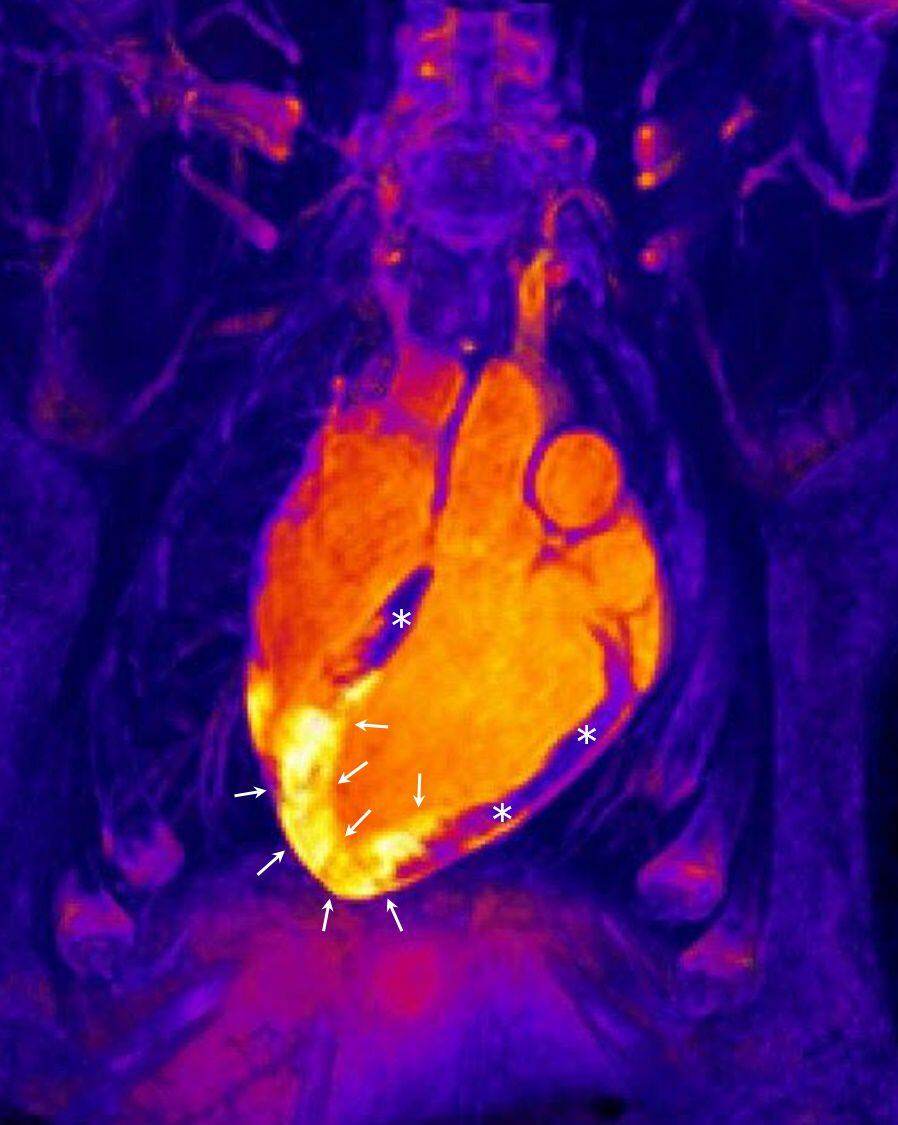

El infarto de miocardio ocurre cuando las células del corazón empiezan a ser dañadas como consecuencia de la obstrucción repentina de una de las arterias que lo alimentan con sangre, esta falta de oxigenación y nutrientes produce la isquemia del músculo cardíaco. Por lo general, la obstrucción ocurre debido a un coágulo formado al romperse una placa de colesterol que se alojaba en la pared de la arteria. En este caso, para desobstruir la arteria se recurre a la angioplastia, una intervención mediante la cual se introduce un catéter con balón para eliminar la obstrucción. Durante el procedimiento, en la gran mayoría de los casos, se coloca un stent. También existen, aunque con un nivel de eficacia inferior, los fármacos trombolíticos que se aplican con el objetivo de disolver el trombo.